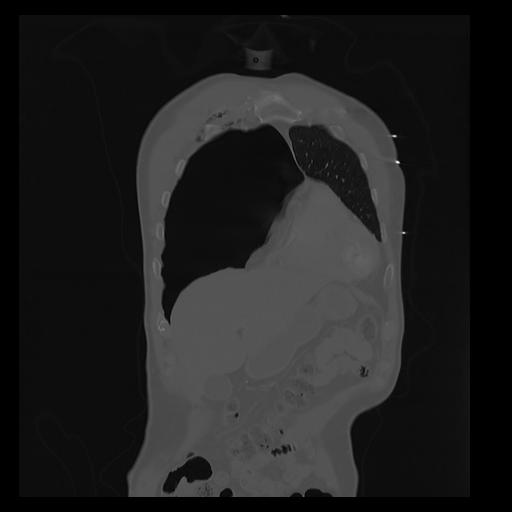

32 PULMON,CE,Coronal,3.000,PULMON,Coronal,